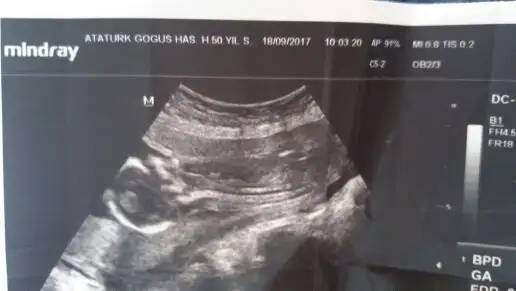

Nursena yazdıklarınının bi kısmını okudum da neredeyse tamamen aynı şeyleri aynı haftalarda yaşıyoruz.Benim serviks uzunluğum alakasız bi karın ağrısı bulantı kusma ile gittiğimde önlem için bakılan usg de 24 mm ölçüldü.Tam 16 haftadayım.Cuma günü kendi doktoruma gittim o da aynı ölçtü aslında gebelik kaybı öyküm yoktu,o bölgeye bi travma da yaşamamıştım ama biraz da değerli gebelik olduğundan doktorum dikiş önerdi.Yüzde yüz gerekiyo gibi konuşmadı ama zarardan çok faydası olur diye düşünerek yaptırdım.Genel anestezi ile yapılıyor zaten sonrasında biraz karın ağrısı oluyo ama ilaçla rahatladım.Beni günlerdir sıkıntıya sokan tek şey progestan iğneler oturup kalkamıyor dönemiyorum genel durumumu da bozdu bulantı baş ağrısı depresyon yaptı.3 gündür kalçalarım beni hayattan soğuttu